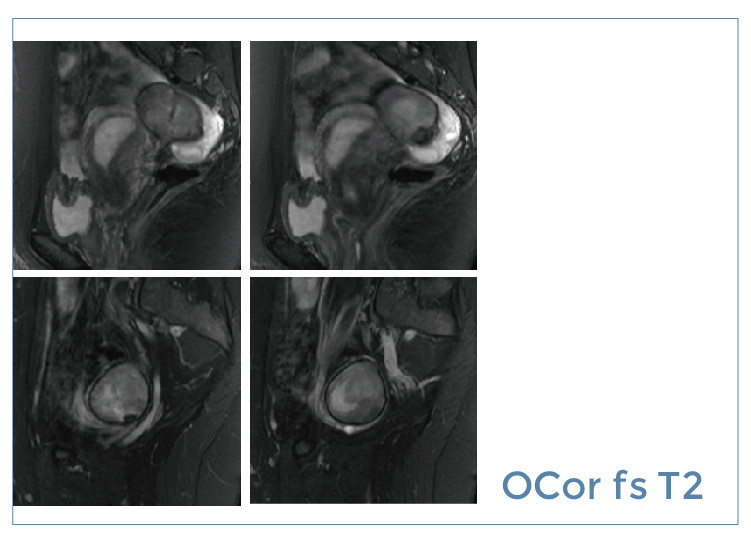

【朗润影像档案】20190705磁共振影像病例结果讨论